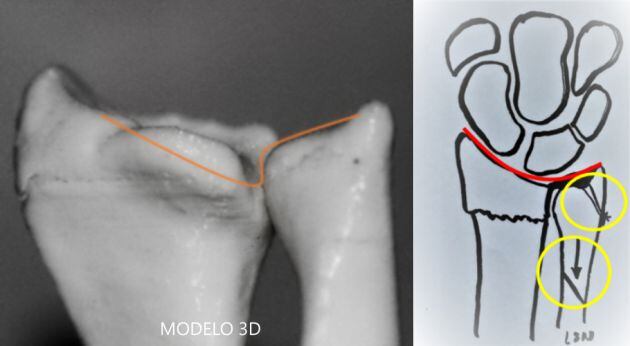

Esta réplica del hueso se entrega a los cirujanos para que puedan ver de un modo real lo que se van a encontrar en la intervención y, así poder planificar la cirugía, elaborar líneas de corte (elegir y modelar los implantes a usar, sean prótesis, placas de osteosíntesis, etc.) y aplicarlas sobre la pieza. Esto permite realizar resecciones con una precisión milimétrica en un espacio que es muy complicado de ver durante la intervención, según el doctor Luis Sánchez Navas, jefe de Traumatología de Quirónsalud Alicante, “esta réplica personalizada reduce mucho el margen de error, disminuye el tiempo quirúrgico y por tanto, las complicaciones derivadas de una larga exposición mejora el porcentaje de éxito de la intervención y la recuperación del paciente porque, al planificar con antelación la forma de la cirugía, consiguen que la intervención se haga en menos tiempo y de un modo más limpio”.

Una de las principales ventajas de la impresión en 3D es que permite una visión espacial de la pieza que se va a extirpar, por ejemplo en el caso de en la artrosis, al quitar el hueso deteriorado se deja el hueco exacto para la prótesis predefinida que se ha planificado implantar, en fracturas se puede reconstruir la fractura como si fuera un puzle, y sobre ella modelar y prever los materiales que sean estrictamente precisos, pudiendo extraer las partes blandas y otros elementos que en cirugía dificultan la visión y manipulación del defecto completo. Esto facilita la realización de un abordaje más seguro, más rápido y mucho más exacto, lo que se traduce en que esa cirugía tendrá mayor probabilidad de conseguir resultados satisfactorios para el paciente y este se recuperará mejor.

Pero, si damos un paso más, no solo se puede obtener maquetas de la anatomía del paciente y su lesión, sino que se pueden diseñar guías, plantillas y herramientas para conseguir una cirugía más rápida y precisa. También ayuda a preparar y probar implantes protésicos, injertos óseos, osteotomías (realización de cortes en un hueso para cambiar su posición, tamaño, corregir curvaturas…) y otras técnicas previas a la cirugía. En definitiva, nos permite realizar una medicina mucho más precisa y personalizada.